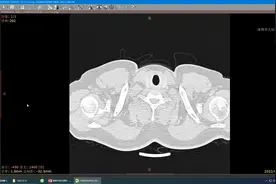

做过B超、拍过胸片、查过CT

全省影像数据准实时集中存储与调阅